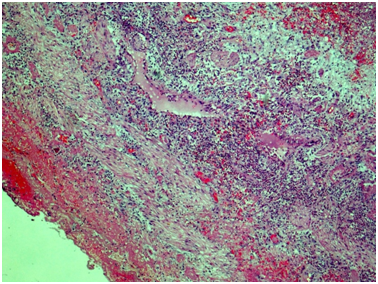

Excised kidney pathology: Light microscopy sections of formalin fixed paraffin embedded tissue were stained with H&E, PAS and Masson’s trichrome.

Kidney: Arterioles and small arteries walls otherwise normal. Middle arteries walls are diffuse thickened due to the fibrous connective tissue with impaired histoarchitectonics of the wall layers and subtotal limen obstruction. Large arteries walls are thickened due to edema, massive transmural and perivascular infiltration with neutrophils and histiocytes, and irregular fibrous connective tissue with impaired histoarchitectonics of the wall layers. Multiple pseudo-aneurisms in the zones of large arteries bifurcation with the severe edema and prominent walls infiltration. Multiple cortical macrofocal ischemic and hemorrhagic renal tissue necrosis. Preserved renal tissue presented by normal glomeruli. Total acute tubulonecrosis without tubular atrophy or interstitial fibrosis (Figures 5 & 6).

Figure 5 Kidney. The wall of a large caliber artery is markedly thickened, forms pseudoaneurismal widening and shows histological architecture disturbance due to the following: edema, dense transmural and perivascular infiltration presented by neutrophilic leukocytes and histiocytes, and irregular coarse fibrosis. Nearby the wall of a medium caliber artery demonstrates severe irregular focal fibrosis with total occlusion of its lumen. Masson’s trichrome; x40.

Figure 6 Kidney. The wall of a medium caliber artery shows histological architecture disturbance due to severe irregular fibrosis with marked luminal narrowing. The upper third of the picture demonstrates cortical necrosis with total ischemic tubular epithelial lesion; nearby the glomerulus is unremarkable. Periodic acid-Schiff, x40.